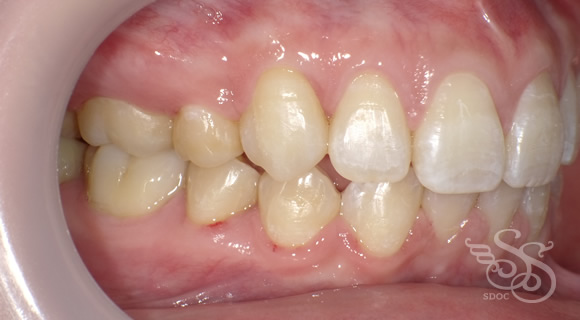

右側:術前

右側:術後

左側:術前

左側:術後

開口(オープンバイト・前歯が閉じない)